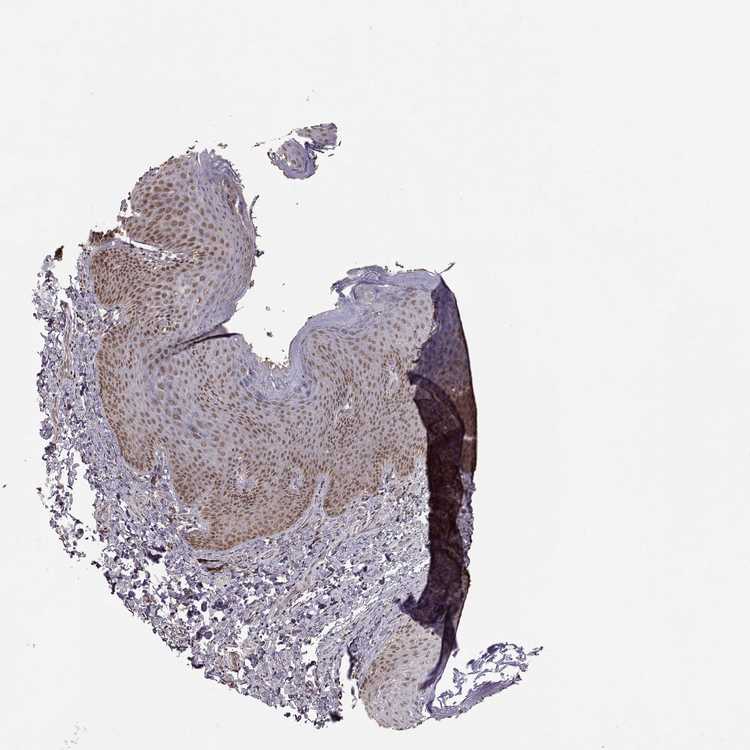

SKIN 2 - Antibody stainingi

Antibody staining in the annotated cell types in the current human tissue is reported as not detected, low, medium, or high, based on conventional immunohistochemistry profiling in selected tissues. This score is based on the combination of the staining intensity and fraction of stained cells.

Each image is clickable and will lead to virtual microscopy that enables deeper exploration of all samples and also displays staining intensity scores, fraction scores and subcellular localization as well as patient and tissue information for each sample.

Antibody HPA069022

Epidermal cells Medium